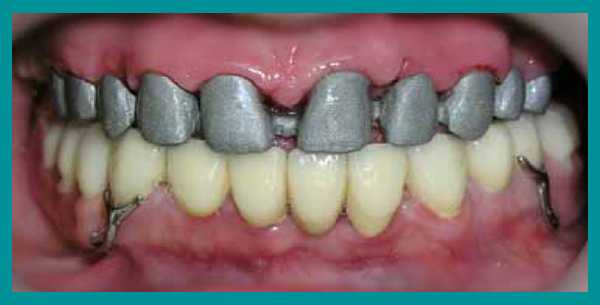

Пациент обратился с жалобами на истирание зубов верхней челюсти и, соответственно, снижение высоты верхних резцов до такой степени, что они перестали быть видны при улыбке. В результате клинического обследования челюстно-лицевой области не выявлено мышечно-фасциальных напряжений, движения нижней челюсти были в полном объеме, симметричные, патологических изменений со стороны ВНЧ сустава не выявлено. Прикус прямой (рис. 1) . На фронтальных зубах верхней челюсти 13—23 определяются окклюзионные фасетки истирания, клиновидные дефекты в области 24 и 25 зубов (рис. 1, 2). Высоту нижних зубов не планировалось изменять, хотя на них также имелись окклюзионные фасетки истирания, но с небольшой потерей тканей (рис. 3, 15) , поэтому прикус повышался без трансверсальных и сагиттальных перемещений нижней челюсти, а именно — в привычной окклюзии только за счет увеличения высоты верхних зубов.